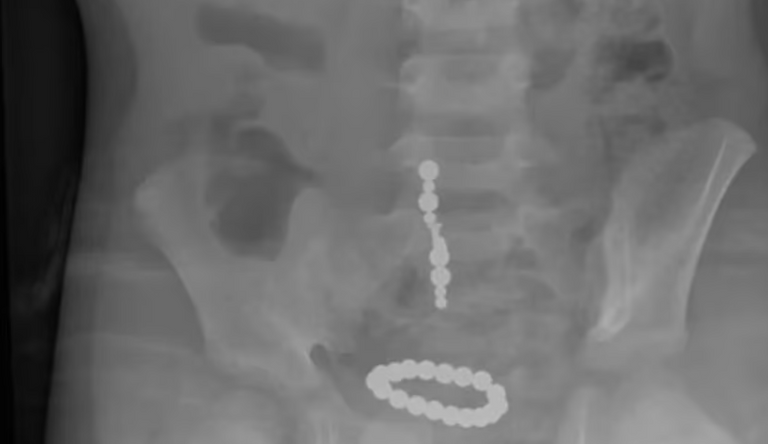

تعتبر الألعاب التي تحتوي على مغناطيسات أيضًا من الأسباب التي تؤدي إلى الحوادث في العطلات. يمكن للأطفال ابتلاع مغناطيسات متعددة، وهو ما يشكل خطرًا أكبر لأن هذه المغناطيسات قد تتجمع معًا داخل الجسم مما يتسبب في انسداد وتمزق الأنسجة والأعضاء.

يقول الدكتور مايكل فلاهرتي، اختصاصي الرعاية الحرجة للأطفال في مستشفى ماس جنرال للأطفال: "هذه المغناطيسات قوية لدرجة أن أجزاء من الأمعاء قد تلتصق ببعضها مما يؤدي إلى حدوث تمزقات أو ثقوب في الأمعاء، وهو ما يتطلب تدخلًا جراحيًا عاجلًا".